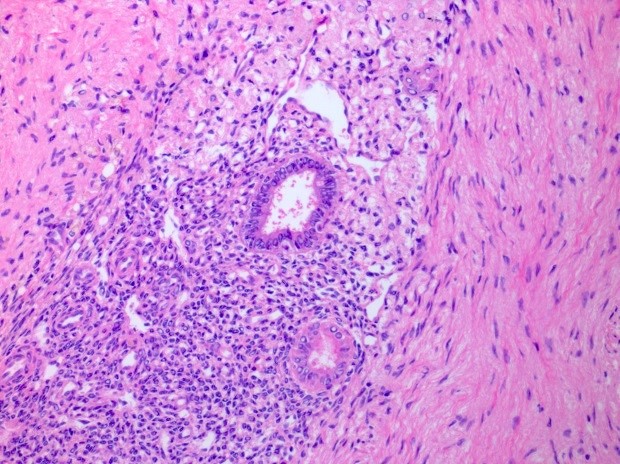

- At least 2 of the following 3 features

- Endometrial type glands

- Müllerian type epithelium (can be atrophic to cycling endometrium)

- Can show degenerative atypia (enlarged smudgy nuclei) or metaplasia

- Endometrial type stroma

- Often contains fine capillary network

- May undergo smooth muscle metaplasia, fibrosis (longstanding), decidual change

- May be myxoid (particularly in pregnancy)

- Stroma may be the only identifiable component (stromal endometriosis)

- Evidence of chronic hemorrhage (hemosiderin laden or foamy macrophages)

- Endometrial type glands

A 39 year old woman presents with pelvic pain and menorrhagia. Hysterectomy was performed and the histologic findings shown in this photomicrograph were present on the serosal surface and right ovary. What malignant neoplasm is most associated with the lesion?

E. Ovarian endometrioid carcinoma. Endometriosis can be associated with endometrioid and clear cell carcinoma, with the greatest association identified in the former neoplasm. Rare endometrial stromal sarcomas and adenosarcomas have also been reported to arise in association with endometriosis. Answer D is incorrect because there is no reported association between germ cell tumors and endometriosis. Answer C is incorrect because there is no reported association between high grade serous carcinoma and endometriosis. Answer A is incorrect because there is no reported association between clear cell sarcoma and endometriosis. Answer B is incorrect because even though some cases of adenosarcomas have been reported to arise in association with endometriosis, the association is less frequent than endometrioid carcinoma.